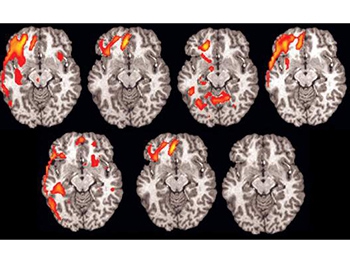

Исследования о возможности разоблачать лжецов при помощи фМРТ, которая позволяет в реальном времени отслеживать приток крови к активным участкам мозга, появились около десяти лет назад. В статье учёных из университета Пенсильвании, опубликованной в Journal of Clinical Psychiatry, приводятся результаты сравнения этого способа и полиграфа: фМРТ оказалось на 24% точнее, чем привычный детектор.

Как оказалось, если человек лжет, активируются участки мозга, ответственные за принятие решений, которые находятся в покое, если человек просто отвечает на вопрос. К активированным участкам приливает кровь, что можно увидеть с помощью функционального магнитно-резонансного томографа.